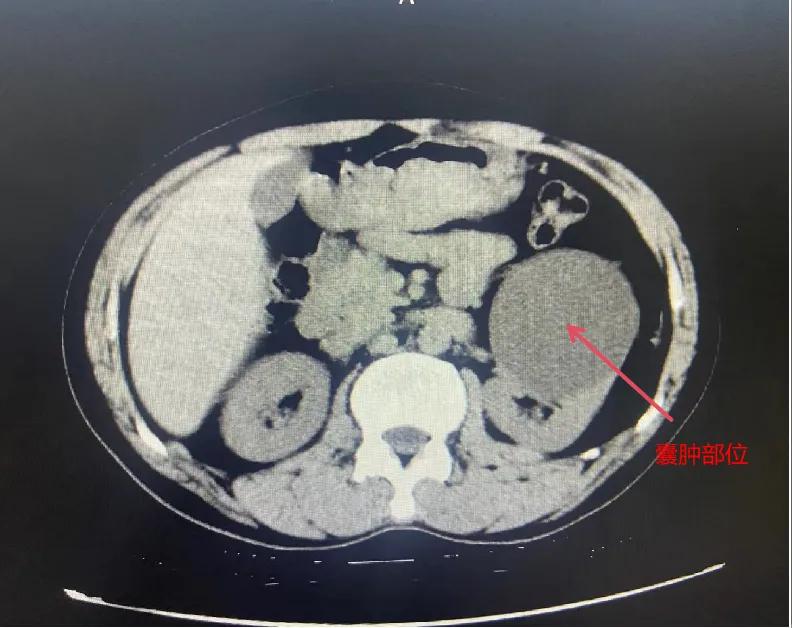

漯河市骨科醫(yī)院泌尿外科開展后腹腔鏡下腎囊腫去頂減壓術(shù)

近日,漯河市骨科醫(yī)院(漯河醫(yī)專二附院、漯河市立醫(yī)院)連續(xù)收治2例腎囊腫患者。泌尿外科主任閆衛(wèi)甫和副主任醫(yī)師王金柱等醫(yī)師團(tuán)隊經(jīng)討論研究后,決定為患者采取后腹腔鏡下腎囊腫去頂減壓術(shù),經(jīng)過手術(shù)室、麻醉科等科室大力配合成功完成手術(shù)。

閆衛(wèi)甫表示,后腹腔鏡技術(shù)是一種微創(chuàng)外科手術(shù)方法,它通過在后腹腔(即腹膜后的空間)建立一個手術(shù)空間,利用腹腔鏡器械進(jìn)行手術(shù)操作。這種技術(shù)特別適用于泌尿系統(tǒng)等后腹腔臟器的手術(shù)。與傳統(tǒng)手術(shù)相比具有創(chuàng)傷小、恢復(fù)快、并發(fā)癥少、視野清晰等優(yōu)點。與前腹腔鏡相比則具有對腹腔臟器干擾較少的優(yōu)點。目前,后腹腔鏡手術(shù)主要用于腎囊腫去頂減壓術(shù)、腎上腺腫瘤切除、早期腎癌根治術(shù)、腎腫瘤剜除術(shù)等。

腎囊腫是一種常見的腎臟良性疾病,其發(fā)病率逐年增加。近年來隨著腹腔鏡技術(shù)的迅速發(fā)展,后腹腔鏡下腎囊腫去頂減壓術(shù)成為治療腎囊腫的主要方法。該手術(shù)具有創(chuàng)傷小,手術(shù)時間短,術(shù)中出血少,術(shù)后康復(fù)快,出院時間短等優(yōu)點,并且術(shù)后復(fù)發(fā)率低,被認(rèn)為是治療腎囊腫的理想術(shù)式。(盧 闖 聶方方 劉 旭 袁錦鈺)